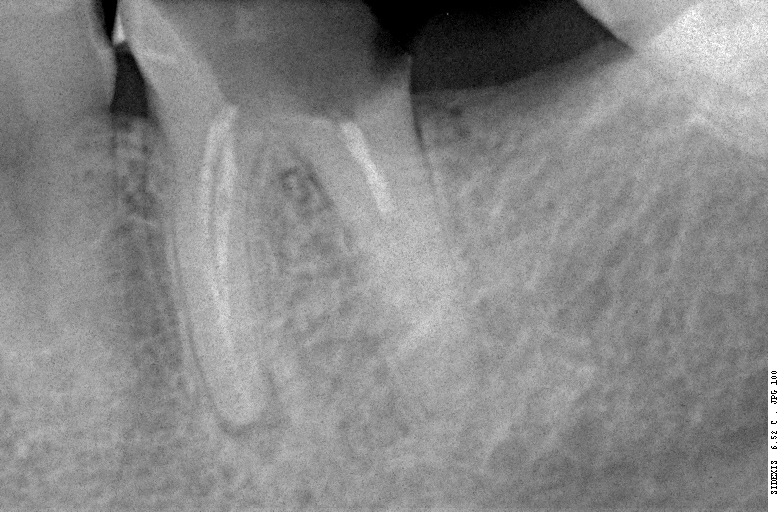

Прицельный радиовизиографический снимок можно сделать в любой из наших клиник. В отличие от обычных прицельных рентгенограмм зубов, доза лучевой нагрузки при проведении подобного исследования в несколько раз ниже, поэтому таких снимков можно сделать очень много. Например, по существующим стандартам, терапевт стоматолог может сделать до десяти снимком зуба в процессе эндодонтического лечения — и это, разумеется, необходимо для качественного лечения каналов зубов.

В хирургической практике я использую прицельные снимки как для первичной диагностики: например, чтобы быстро понять локализацию ретинированного зуба мудрости и его отношение к окружающим структурам, либо для интра- и послеоперационного контроля результатов имплантологического лечения. А наличие цифровой базы радиовизиографических снимков позволяет понять, как ведет себя протез на импланте в течение длительного времени: